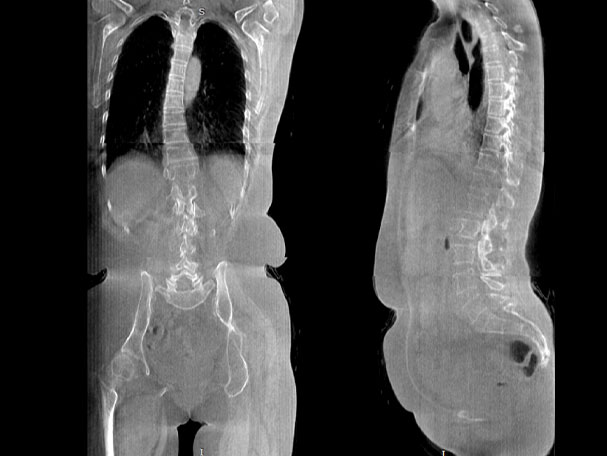

· 补位CT,提供负重位三维影像

· 引领普放走向三维精准诊断时代

填补常规CT/MR空白

助力术前规划和术后评估

腰椎